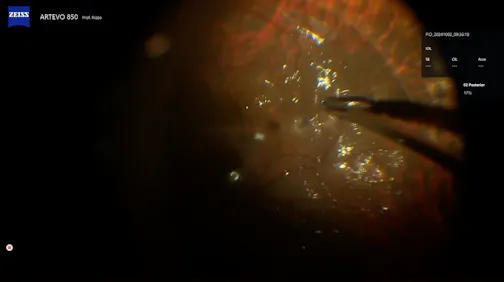

Two IOLs

Chi-Chun Lai, MD